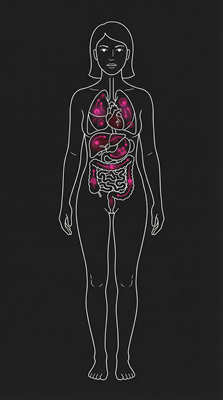

Anti-Cancer Potential

In vitro studies show cytotoxic effects against various cancer cell lines, linked to stigmasterol, β-sitosterol, and squalene.

Antimicrobial Activity

Extracts show activity against Gram-positive (e.g., Staphylococcus aureus) and Gram-negative (e.g., Pseudomonas aeruginosa) bacteria.

Antidiabetic & Nephroprotective Effects

Black truffle modulates oxidative stress and cytokines via Nrf2 pathway, showing antidiabetic and kidney-protective activity.

Immune System Support

Polysaccharides help regulate and strengthen immunity against infections and disease.

Digestive Health

High dietary fiber (7–15g/100g) promotes regular bowel movements and prebiotic effects.

Neurological & Aphrodisiac Effects

Anandamide ("bliss molecule") supports mood & appetite regulation. Androstenol historically used as aphrodisiac via aroma stimulation.